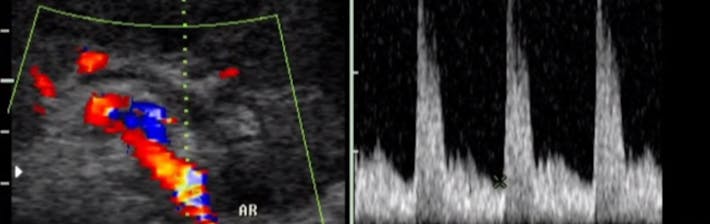

La ecografía doppler o eco-Doppler, emplea ultrasonidos y el efecto Doppler para poder visualizar la velocidad del flujo de los vasos sanguíneos